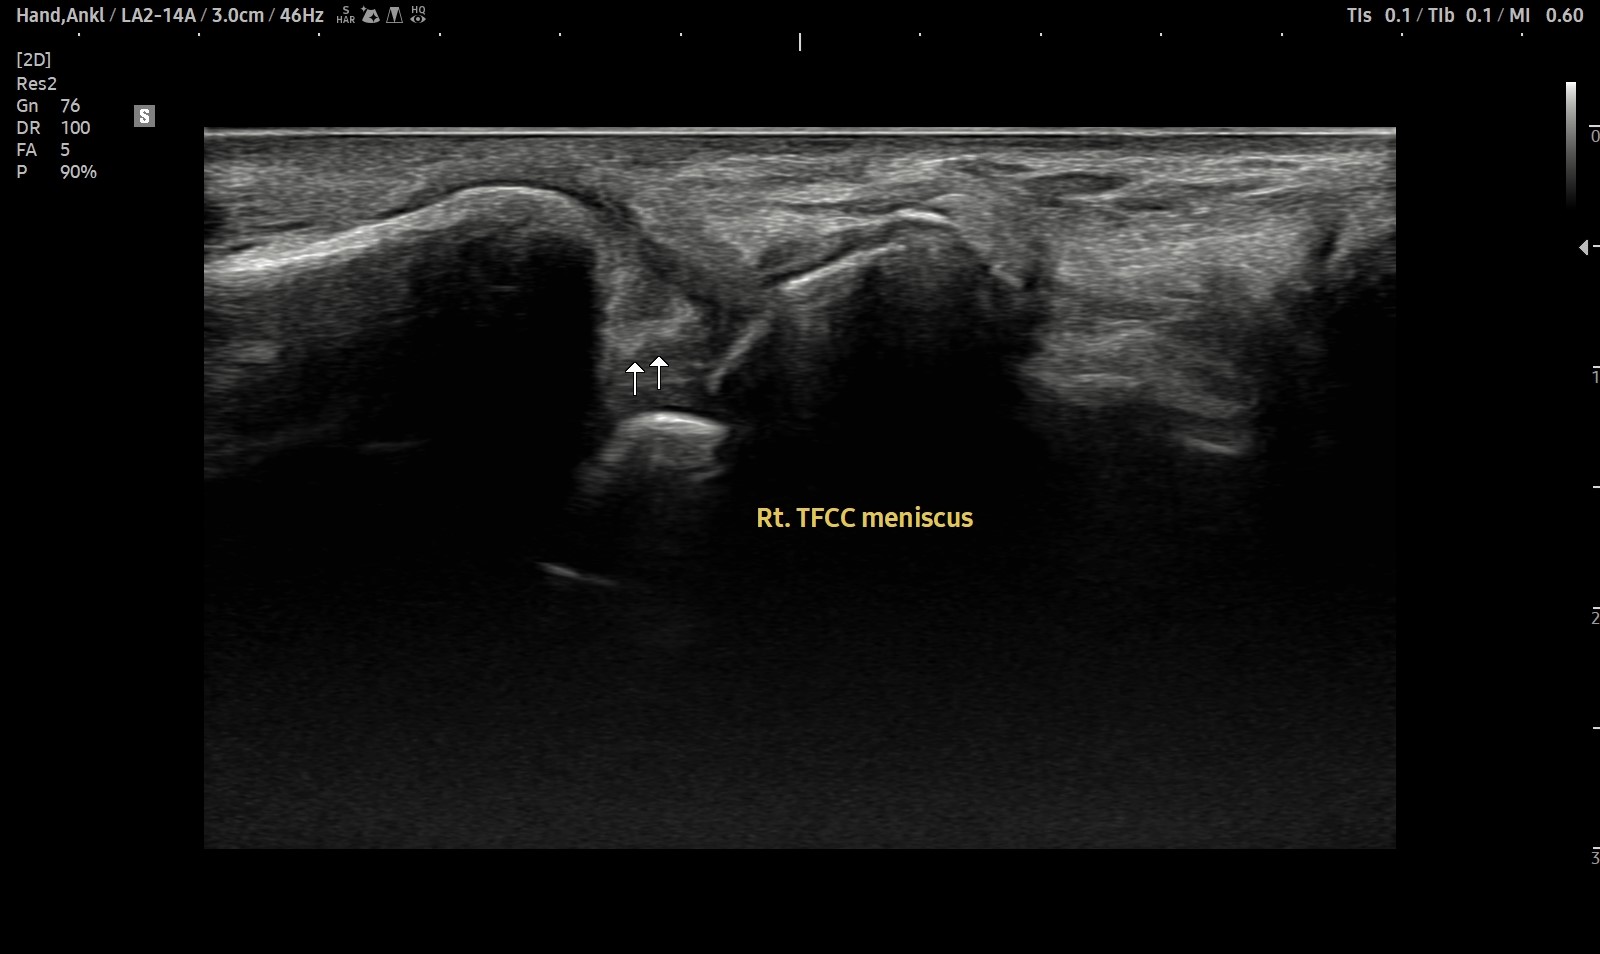

- 치료기간 : 25 . 5 . 7 ~ 25 . 8 .12

- 치료횟수 : 4cycle(20) 회

치료전

치료후